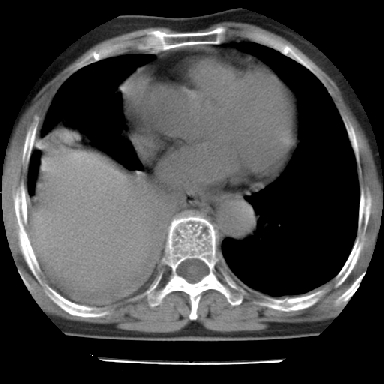

以下是引用苯小孩在2007-4-13 16:20:00的发言:[br]1、右下肺中央型肺癌并阻塞性肺不张、肺内转移、胸椎右侧附件亦有转移<横断层面第8层>.[br]2、右侧胸腔积液.

以下是引用swyyy2007在2007-4-13 15:31:00的发言:[br]右肺门下区肿块,右肺下叶支气管阻塞,右肺下叶不张,右侧大量胸腔积液,右肺中叶见结节状高密度影,边缘清,纵隔内见肿大淋巴结。首先考虑右下肺中心型肺癌伴右肺下叶不张、中叶、纵隔淋巴结转移。右侧胸腔积液。